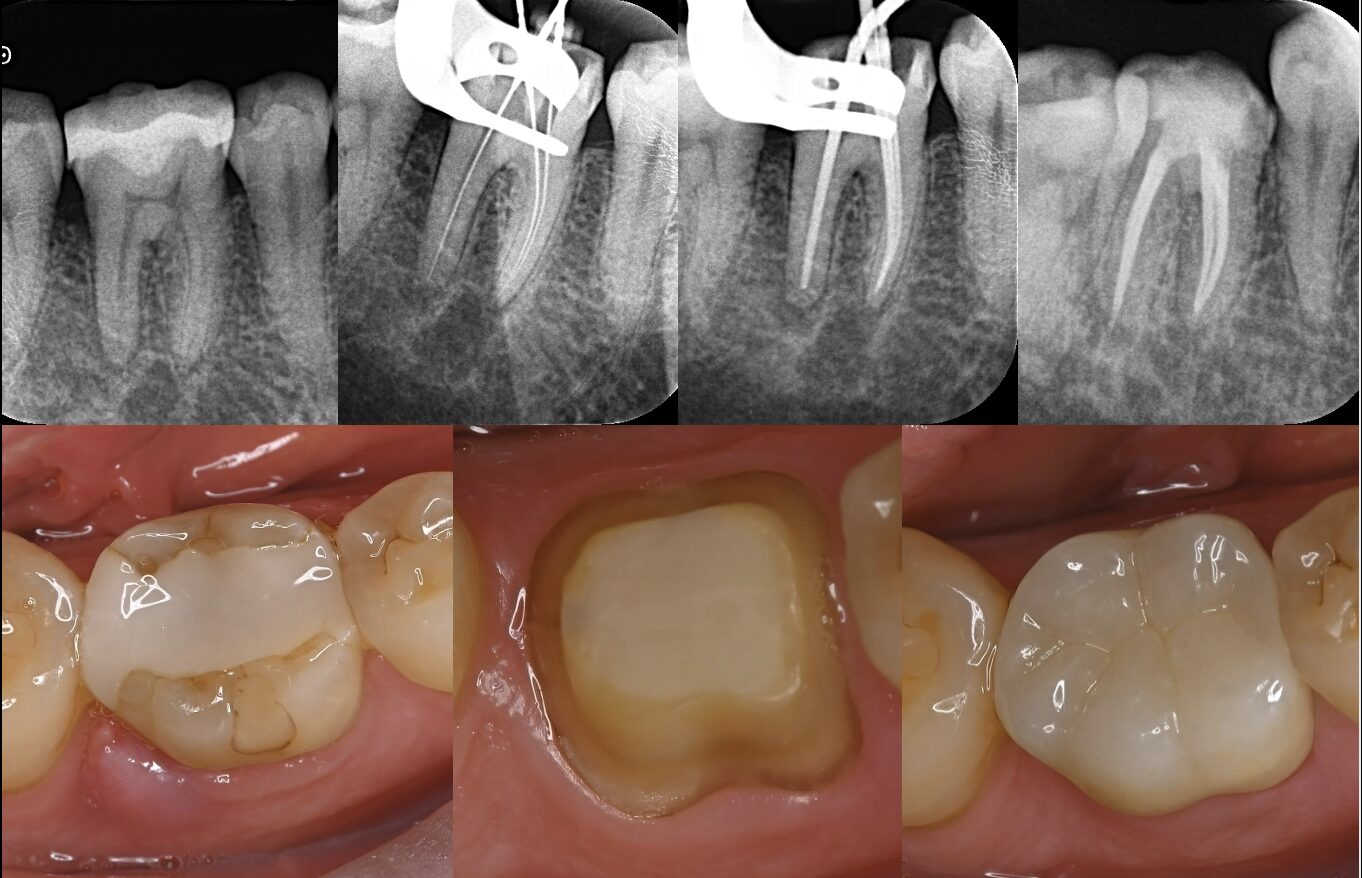

以下の患者様は、根管治療を開始したものの痛みがひかず、また口の中から強い薬のにおいがするとのことで髙井歯科クリニックを受診されました。虫歯が残っている状態であり、治療によって痛みは完全に消失し、良好な経過をたどっています。

初診来院時のやりとりと、実際の治療の経過についてご紹介します。

実際の治療の経過:他院で根管治療を開始したが、痛みが強く続いているため転院【40代女性】_症例25>>